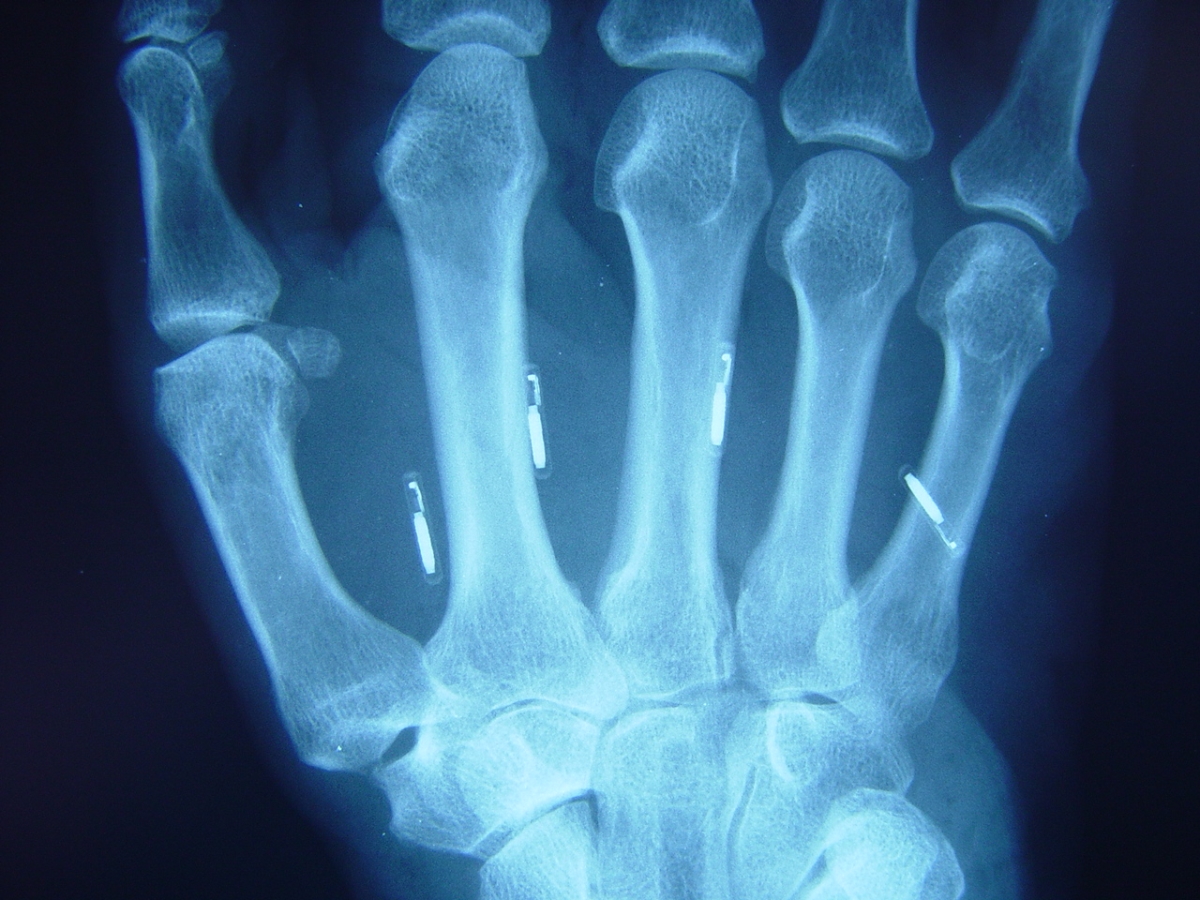

Clinical Example: RFID chips in the hand

Radiofrequency Identification Chip (RFID) technology is advancing both in and out of biologic applications. These are pictures of prototype implantable RFID devices designed to link handgun activation to the hand of the owner.